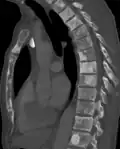

Osteosclerosis is a disorder characterized by abnormal hardening of bone and an elevation in bone density. It may predominantly affect the medullary portion and/or cortex of bone. Plain radiographs are a valuable tool for detecting and classifying osteosclerotic disorders.[1][2] It can manifest in localized or generalized osteosclerosis. Localized osteosclerosis can be caused by Legg–Calvé–Perthes disease, sickle-cell disease and osteoarthritis among others. Osteosclerosis can be classified in accordance with the causative factor into acquired and hereditary.[2][1]

Osteosclerosis can be detected with a simple radiography. There are white portions of the bone which appear due to the increased number of bone trabeculae.